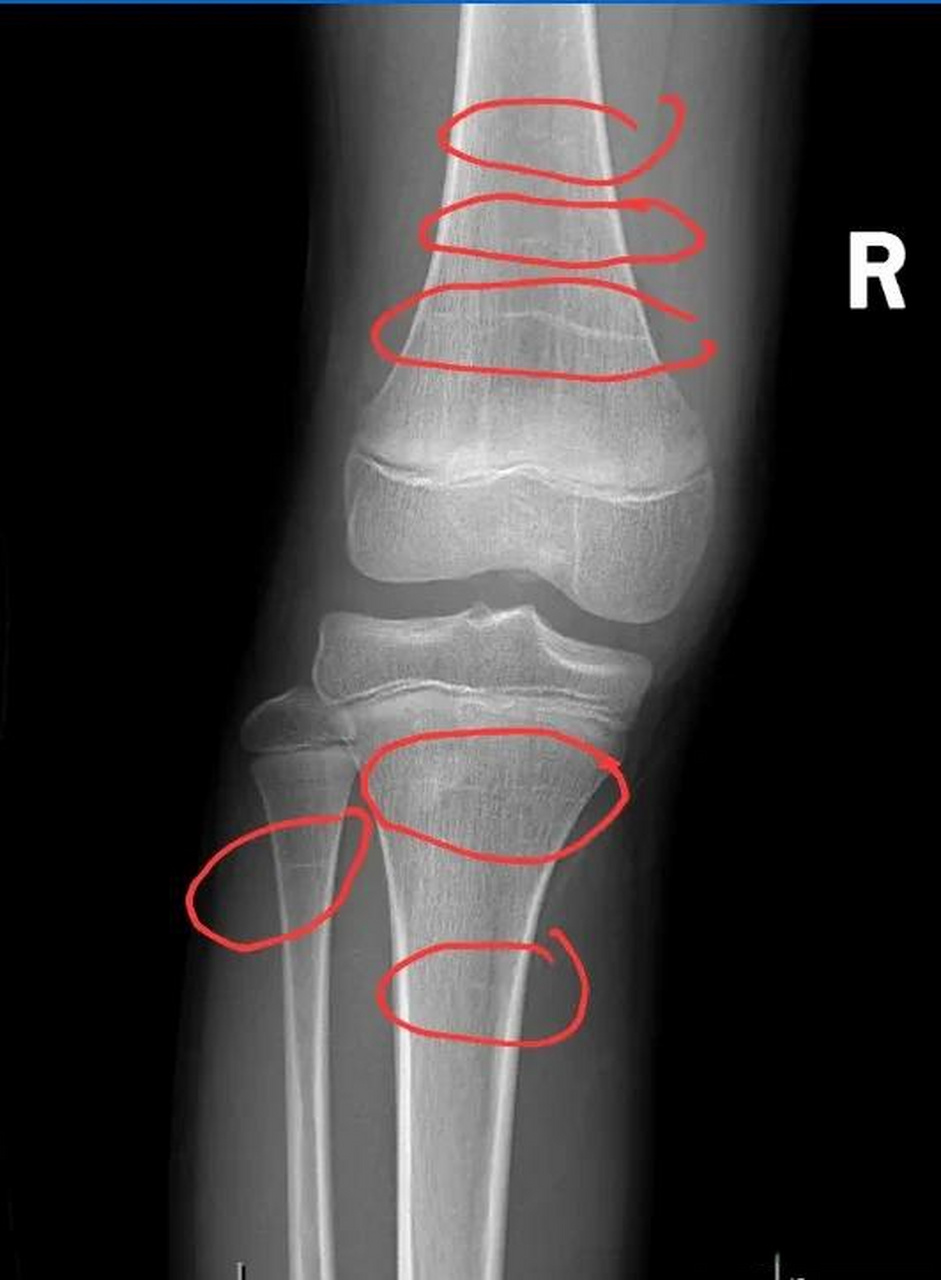

在医院拍的膝盖拍片,我想问问骨骺线闭合了吗?

五月份十六岁,男生 前几天拍的片子,我想知道我的膝盖骨骺线闭合了吗?

医生您好,请帮我看下我的膝盖骨骺线有没有闭合,非常感谢!

生长障碍线(图中患者女,17岁,膝关节偶尔不明原因疼痛) 生长障碍线